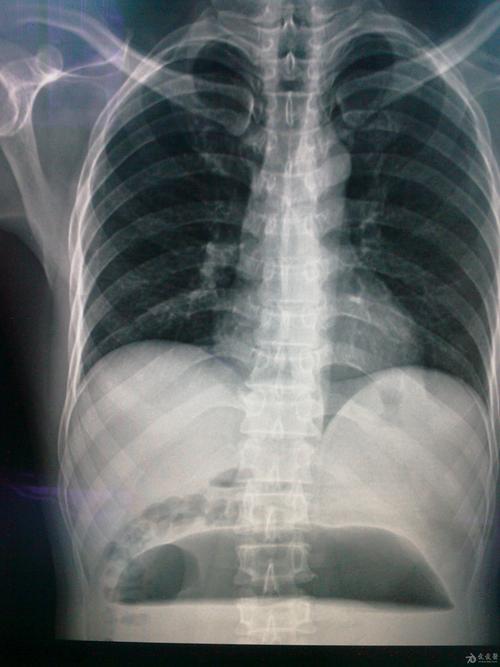

门诊dr腹部立位片提示:肠管积气,多个气液平面.

腹部一长液气平面